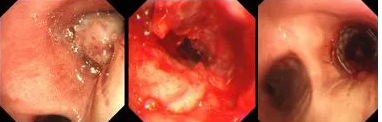

氣短、胸悶、呼吸困難,80歲的患者秦爺爺已經(jīng)出現(xiàn)了瀕死癥狀;局麻、右主支氣管再通,僅用6秒,胸科專家順利實施TTS氣道支架手術(shù)。

原來,秦爺爺入院時診斷為“右主支氣管”鱗狀細(xì)胞癌伴壞死。他的右主支氣管被腫瘤完全堵塞,混合性狹窄。面罩吸氧10升/分的狀況下,指脈氧只有85%,無法平躺,呼吸困難,病情十分危急,隨時有生命危險。

經(jīng)評估并與家屬溝通同意后,歐陽海峰副院長決定為患者實施TTS氣道支架手術(shù)。手術(shù)當(dāng)天,在麻醉手術(shù)中心的配合下,歐陽海峰副院長為患者在局麻下快速凍切腫瘤組織,實現(xiàn)右主支氣管再通,并經(jīng)氣管鏡活檢孔道迅速植入14*30 TTS支架一枚。支架植入過程耗時僅6秒,迅速緩解了患者的氣短瀕死癥狀。